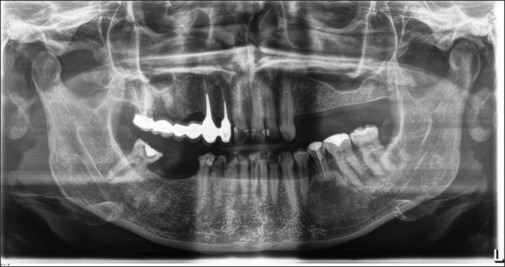

Fibrous dysplasia is a rare genetic syndrome that affects bone tissue. This pathology replaces the mineralized matrix of the bone affected with connective and fibrous tissue. This article describes a mandibular fibrous osseous dysplasia case and its surgical treatment. A 45-year-old woman complained about a slow development of swelling of the left mandibular bone. The orthopantomography (OPT) and the cone beam computed tomography (CBCT) revealed a well-circumscribed sclerotic lesion with a ground-glass appearance apical to the 3.5 element. The surgery was performed to excise the lesion. Anatomopathological examination of tissue confirmed the suspects among the diagnosis of fibrous dysplasia. The patient underwent to follow-up of 4 years, and no recurrences were found. In the absence of a univocal consensus on therapy, surgery remains the treatment of choice for unifocal forms.